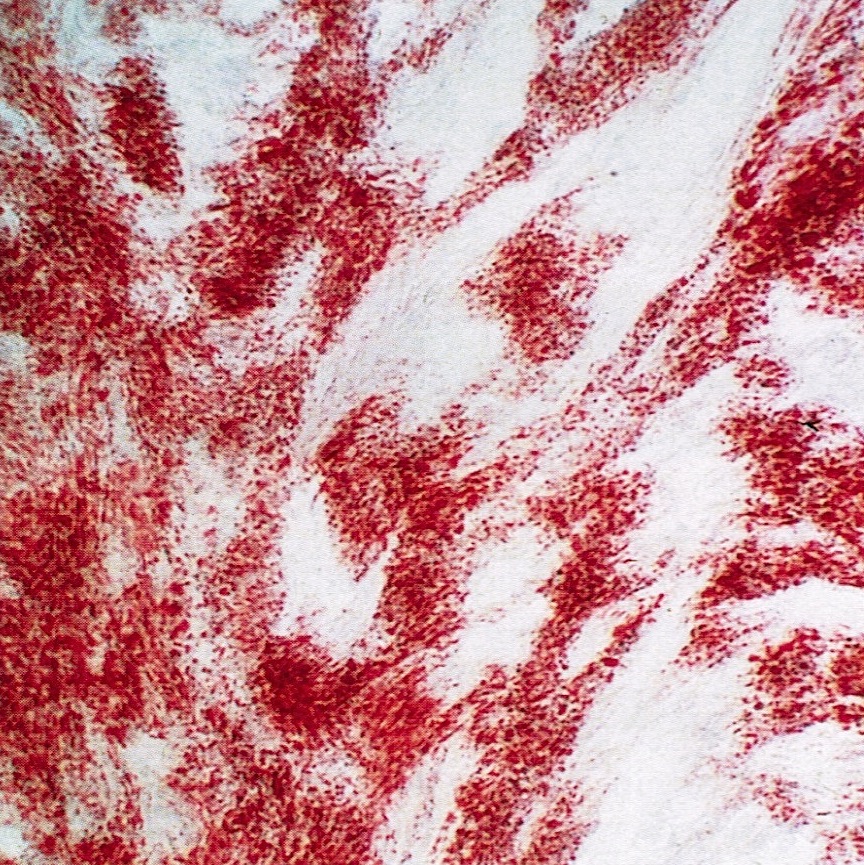

Microscopic (histologic) images

Contributed by Victoria Collins, M.D., Tamara Kalir, M.D., Ph.D., AFIP and @SeoparjooAzmel on Twitter

Positive stains

- Reticulin stain shows a pericellular pattern (Int J Gynecol Pathol 2018;37:305)